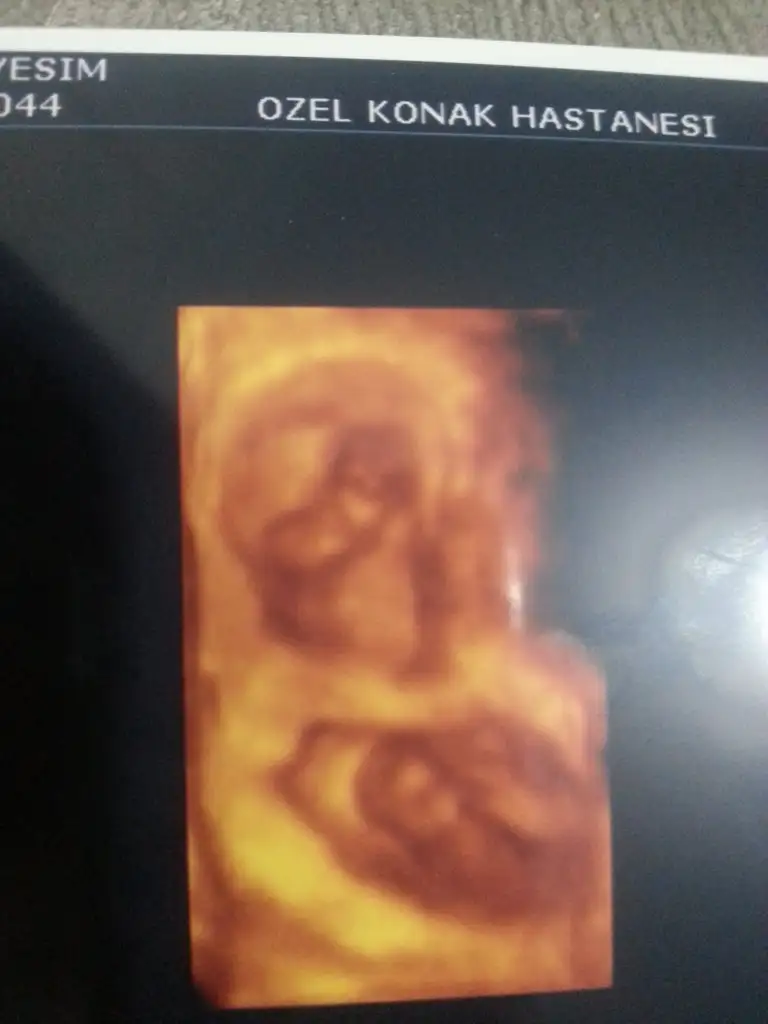

dr soylemeden siz gorun genital nub teorisi ( bebegin cinsiyeti)

Evveet teyzoşlarıı yorumları alalım bu arada ikiz olduğu için orda iki bebek var ama bende hangisi 1 hangisi 2 bilmiyorum

Benim bebişlerime tahmin yok muu teyzeleri

Bana erkek gibi geldi. Sağlıkla gelsin inşallah :)